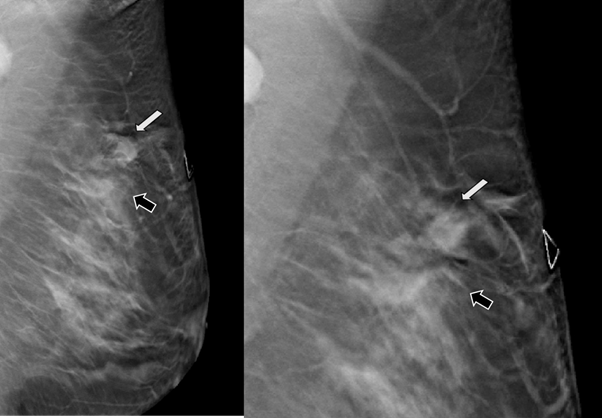

Figure 9 Craneocaudal projection, gray-scale ultrasound and color Doppler images.

A) In the year 2014, the PSA is a dense, round nodule with circumscribed margins (arrow). In the Gary-scale ultrasound a tiny microcalcification is seen within the nodule. PSA is round, hypoechogenic and with circumscribed margins. Using color Doppler, aliasing phenomenon is observed because the vascularity shows high velocity flow, which reflects the arterial nutrition.

B) In the year 2018, the PSA became less dense respect to the previous images (arrow). In the Gary-scale ultrasound, the nodule presents peripheral microcalcifications. Using color Doppler, the nodule is avascular and internal vascularity is demonstrated at the nutrient artery of PSA.

C) In the year 2020, coarse microcalcification is seen within the hypodense nodule (arrow). In the Gary-scale ultrasound, the nodule shows a echogenic rim. Using color Doppler, low vascularity is seen in the PSA.

D) In the year 2022, a greater coarse microcalcifcations is seen within the hypodense nodule (arrow). In the Gary-scale ultrasound, the nodule shows a coarse microcalcifications that creates posterior acoustic shadowing. Using color Doppler, the PSA is avascular which is thrombosed.